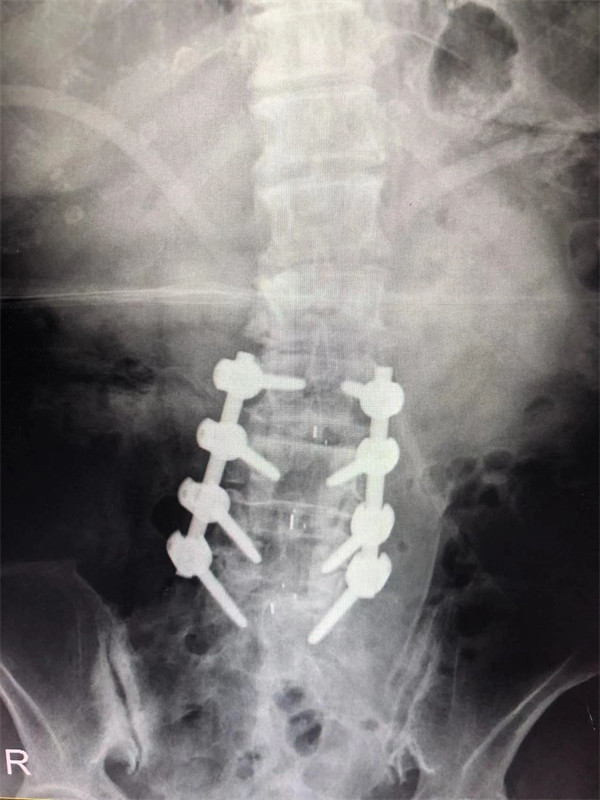

戈才華主任團(tuán)隊(duì)討論病情及手術(shù)風(fēng)險(xiǎn),并與麻醉科醫(yī)生多次討論術(shù)中麻醉風(fēng)險(xiǎn),經(jīng)過(guò)詳盡周密的布置之后,最終給阿婆在全麻下進(jìn)行腰3/4,4/5,腰5/骶1腰椎椎體間融合術(shù)。

手術(shù)后↓